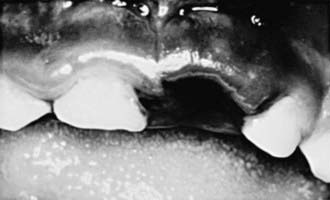

Intruded teeth are pushed up into their socket, sometimes to the point where they are not clinically visible. Intruded primary incisors can give the false appearance of being avulsed (knocked out). To rule out avulsion, a dental radiograph is indicated (Figs. 306-2 and 306-3).

image

Figure 306-2 Intruded primary incisor that appears avulsed (knocked out).